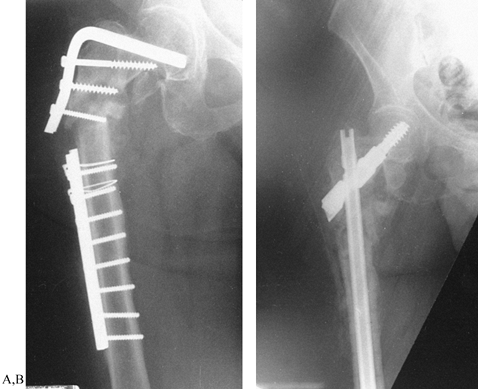

Figure 30.2. A:

AP radiograph of a subtrochanteric nonunion after blade plate fixation

of a comminuted subtrochanteric fracture with failure of the plate. B: AP radiograph showing treatment with an Alta rod connector combined with a hip screw and an autologous bone graft.

Figure 30.3. A:

AP radiograph of a 45-year-old man 1 year after ipsilateral concomitant

fracture of the femoral neck and shaft treated with an Alta rod

connector. There was union of the femoral neck and nonunion of the

shaft fracture. B: The nonunion was

treated by removal of the rod connector and repeat closed nailing with

a larger nail with static locking in compression. This AP radiograph

shows union 9 months after repeat nailing.